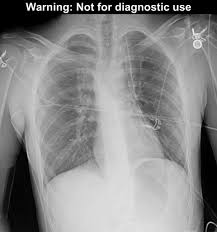

Pneumothorax / Case Report Covid 19 Associated Bilateral Spontaneous Pneumothorax A Literature Review In The American Journal Of Tropical Medicine And Hygiene Volume 103 Issue 3 2020 / Tension pneumothorax most commonly occurs in people with penetrating chest injuries.. This may be caused by physical trauma to the lung, such as a wound. Pneumothorax nursing interventions, treatment, pathophysiology nclex review for the different types of pneumothorax: There are several variations of pneumothorax. Pneumothorax is the medical term for a collapsed lung, a condition in which air or gas is trapped in the space surrounding the lungs causing the lungs to collapse. Also known as pneumothorax, collapsed lung is a rare condition that may cause chest pain and make it hard to breathe.

This is termed spontaneous pneumothorax. Pneumothoraces can be even further classified as simple, tension, or open. Pneumothorax nursing interventions, treatment, pathophysiology nclex review for the different types of pneumothorax: Pneumothorax, also called a collapsed lung, is when air gets between one of your lungs and the wall of your chest. It is reasonably common and has many different causes.

Scielo Brasil Pneumothorax As A Late Complication Of Covid 19 Pneumothorax As A Late Complication Of Covid 19 from minio.scielo.br In tension pneumothorax, patients are distressed with rapid laboured respirations, cyanosis, profuse diaphoresis, and tachycardia. The definition of a pneumothorax is an accumulation of air outside the lungs, but inside the chest wall. Tension pneumothorax most commonly occurs in people with penetrating chest injuries. In a healthy body, the lungs are touching the walls of the chest. Patients with a pneumothorax typically report dyspnoea and chest pain. A pneumothorax occurs when air leaks into the space between the lung and chest wall (called the pleural space). A small pneumothorax may cause few or no symptoms. Pneumothorax occurs when air enters the space around your lungs (the pleural space).

While secondary pneumothorax is caused by an underlying pulmonary disease, the spontaneous type occurs in healthy individuals without obvious cause. When there is no apparent cause, the condition is known as spontaneous pneumothorax. Other signals that the problem may be a collapsed lung are: Pneumothorax is classified as spontaneous or traumatic. Normally, the outer surface of the lung sits next to the inner surface of the chest wall. There are several variations of pneumothorax. It occurs when air accumulates between the parietal and visceral pleura inside the chest. A tension pneumothorax can cause complete collapse of the nearby lung and can push the heart and major blood vessels to the other side of the chest. A collapsed lung requires immediate medical care. Patients with a pneumothorax typically report dyspnoea and chest pain. This air pushes on the outside of your lung and makes it collapse. The lung and the chest wall are covered by thin membranes called pleura. Also known as pneumothorax, collapsed lung is a rare condition that may cause chest pain and make it hard to breathe.

Pneumothorax And Pneumomediastinum In Covid 19 A Case Series The American Journal Of The Medical Sciences from els-jbs-prod-cdn.jbs.elsevierhealth.com A collapsed lung requires immediate medical care. Other signals that the problem may be a collapsed lung are: Patients with a pneumothorax typically report dyspnoea and chest pain. In a healthy body, the lungs are touching the walls of the chest. Pneumothorax is classified as spontaneous or traumatic. A pneumothorax is commonly known as a collapsed lung. A pneumothorax is an abnormal collection of air in the pleural space between the lung and the chest wall. This air pushes on the outside of your lung and makes it collapse.